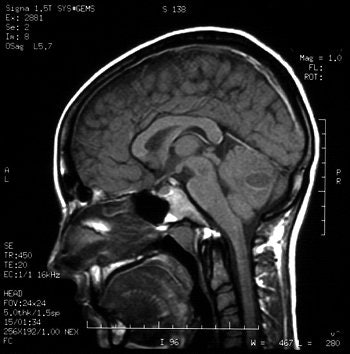

Gadolinium-enhanced MRI scans confirmed the presence of a cerebellar brain abscess in a 22-year-old woman who had undergone tongue piercing four weeks earlier. Images courtesy of Dr Richard Martinello.

However, a brain CT scan revealed a "right cerebellar enhancing lesion with surrounding edema, and an MRI scan with gadolinium confirmed the presence of a solitary brain abscess," the authors reported. The patient underwent a right suboccipital craniotomy to drain the abscess and was then treated with antibiotics. A follow-up CT showed complete resolution of the abscess.